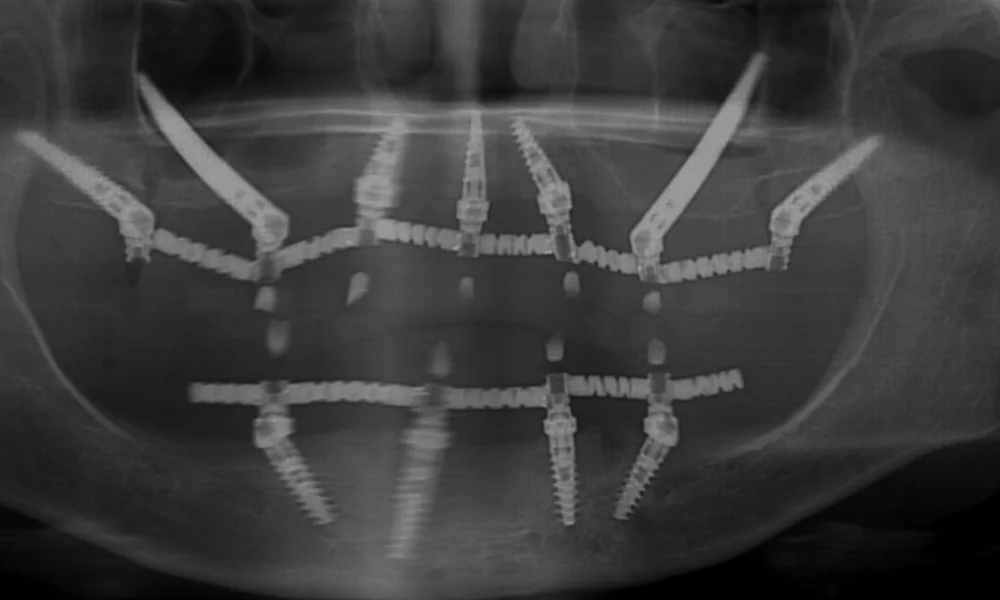

בשתלים רגילים, השתל מוברג לתוך עצם הלסת, שצלים זיגונטיים, לעומת זאת, הם שתלים ארוכים יותר משתלים רגילים ומגיעים אל מעל לאזור הלסת. כלומר אל עצם הזיגומה – העצם שממוקמת בחלק העליון של הלחי, היכן שנמצאת הגבעה של הלחי.

השתלה זיגומטית מצריכה מיומנות גבוהה מצד הרופא, שכן על הרופא להחדיר את השתל בצורה מדויקת אל תוך עצם הזיגומה.

בתהליך זה, הרופא נדרש לבצע חיתוך מדויק של החניכיים, ולאחר מכן להחדיר את השתל הזיגומטי לעמקי העצם הזיגומטית. בעזרת שתלים ארוכים יותר וברגים מיוחדים, השתל "ננעץ" בתוך העצם בצורה יציבה ומאפשר עיגון מוצלח של השיניים.